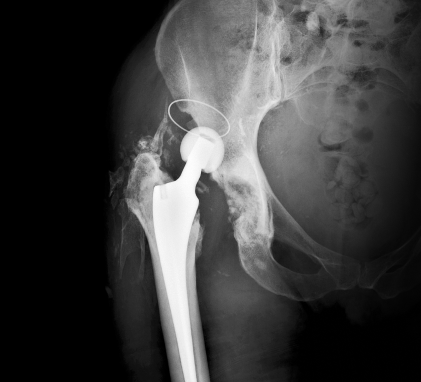

무릎인공관절

엉덩이마디 질환